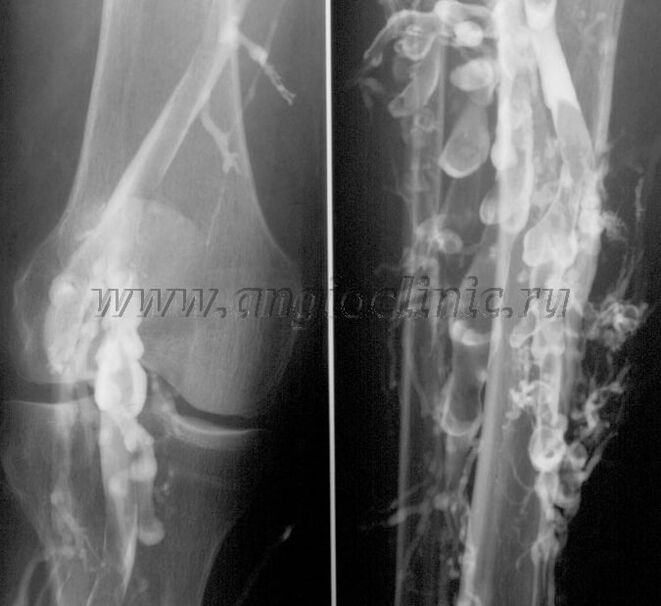

Kontrastna venografija

Obično je ultrazvučno skeniranje dovoljno za potpunu dijagnozu venske patologije, ali je u nekim slučajevima potrebno proučiti odnos između stanja dubokog i površnog venskog sistema, posebno u slučaju relapsa proširenih vena i sekundarnih proširenih vena.

Ultrazvučno skeniranje

Za rješavanje ovih problema koristi se kontrastni rendgenski pregled. Safenozne vene se punktiraju i daje se kontrast. Na monitoru rendgenskog aparata se posmatra kretanje kontrasta i vrše se svi potrebni testovi i projekcije. Trenutno se venografija za proširene vene koristi vrlo rijetko.